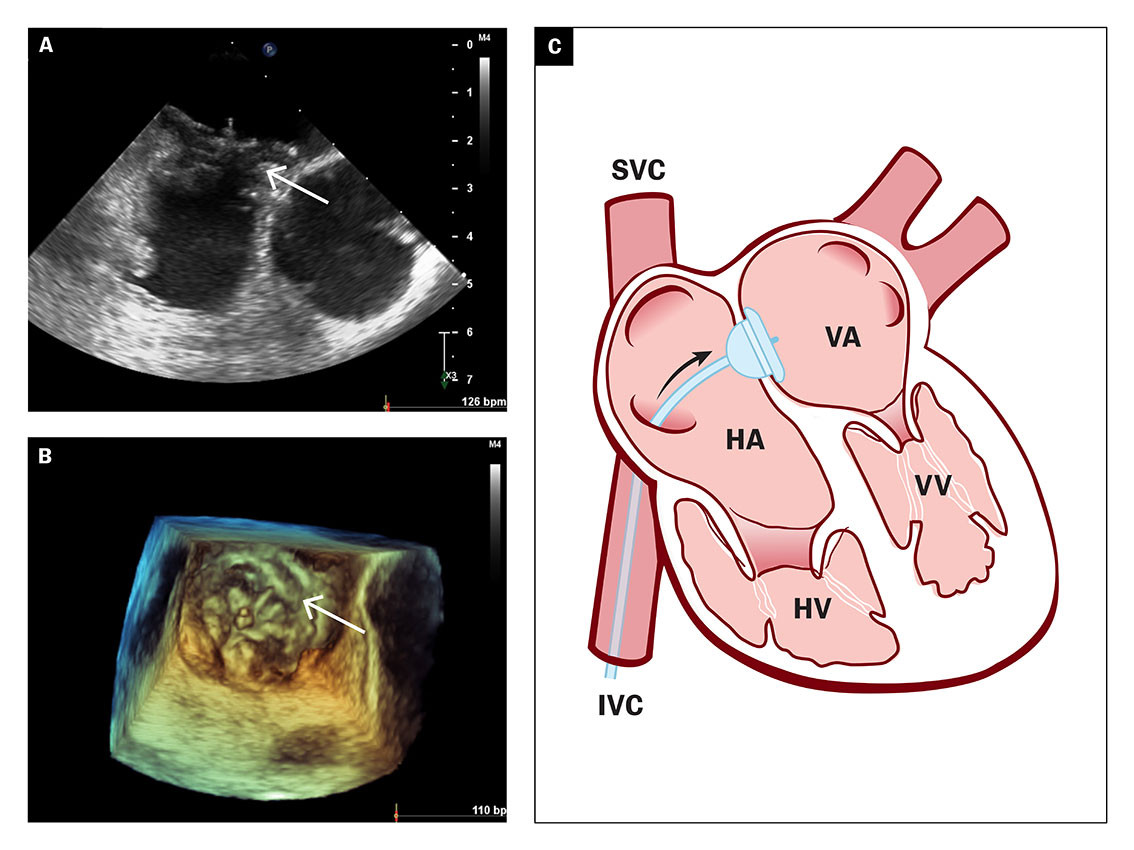

Transøsofageal ekkokardiografi viste et åpentstående foramen ovale med kanallengde 10 mm og åpning på 5 mm (figur 3a) og et hypermobilt atrieseptum. Det var spontan shunt fra høyre atrium til venstre atrium bedømt med fargedoppler (figur 3b).

Funnene på transøsofageal ekkokardiografi støttet mistanken om paradoksal embolisering med overgang av trombe fra høyre til venstre atrium. Åpentstående foramen ovale verifiseres vanligvis ved å injisere agitert saltvann i perifer vene og be pasienten utføre Valsalvas manøver. Økt venøs retur til høyre atrium vil da gi en forbigående økning i atrietrykket som kan gi overgang av mikrobobler fra høyre atrium til venstre atrium (figur 3c).

Grunnet tydelig spontanshunt fra høyre til venstre side ble det ikke gjort bobletest hos denne pasienten. Hun ble vurdert for perkutan kateterbasert lukking av åpentstående foramen ovale for å redusere risikoen for fremtidig arteriell embolisering. Som ledd i utredningen fikk pasienten også utført ultralyd av dype vener. Denne avdekket bilaterale tromber i leggvener som ble beskrevet som mobile og med et kronisk utseende. MR cerebri og øyebunnsundersøkelse gav ikke holdepunkt for ferske emboliske infarkt cerebralt eller retinalt.

Pasienten ble skrevet ut fra sykehuset etter åtte dagers opphold med antikoagulasjonsbehandling i form av apiksabantabletter peroralt og henvist til elektiv kateterbasert lukking av åpentstående foramen ovale. Det ble ved ballongmåling av åpentstående foramen ovale funnet kort kanal med diameter på 15 mm, som ble lukket perkutant med en 30 mm GORE Septal Occluder (figur 4a–b), et selvekspanderende implantat laget av nitinol og goretex, med to flater som lukker seg inntil hver side av atrieseptum (figur 4c).